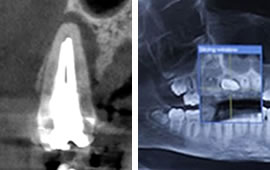

歯内療法(しないりょうほう)とは、神経の治療、歯の根っこの治療全般のことを指します。神経の治療、歯の根っこの治療といってもその種類は多様です。重度の虫歯や歯にヒビが入ってしまった場合などに、神経の通っている穴が感染をおこす場合がありますが、そういった時に行うのは歯内療法のうちの一つである根管治療と呼びます。根管治療の他にも、神経を抜かないようにするための歯髄保存療法や、外科処置を行う外科的歯内療法など多種ございます。